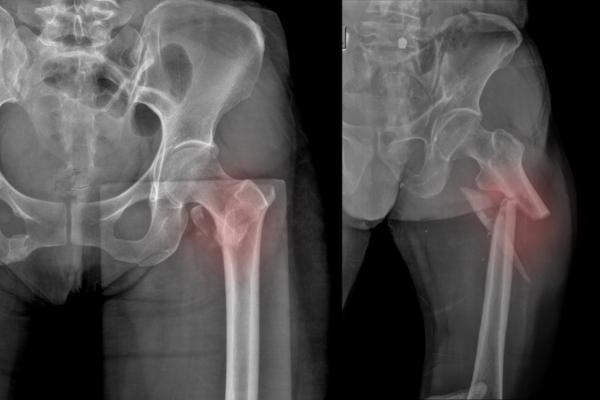

Ως κάταγμα ισχίου ορίζεται το σπάσιμο στο άνω τμήμα του μηριαίου οστού και τα αίτια πρόκλησής του εξαρτώνται από την ηλικία του ασθενούς. Για την πρόκληση καταγμάτων ισχίου στις μεγαλύτερες ηλικίες ευθύνονται κυρίως πτώσεις, ακόμη και από μικρό ύψος. Τα οστά των ηλικιωμένων ασθενών που πάσχουν από οστεοπόρωση χάνουν την πυκνότητά τους και είναι εξαιρετικά εύθραυστα. Επομένως, μια πτώση από μηδαμινό ύψος είναι αρκετή για την πρόκληση ενός κατάγματος ισχίου. Στους νεότερους ασθενείς τα κατάγματα ισχίου προκαλούνται συνήθως εξαιτίας τροχαίων ατυχημάτων.

Ανάλογα με το σημείο που εντοπίζονται τα κατάγματα ισχίου διακρίνονται στα παρακάτω είδη:

- Υποκεφαλικό κάταγμα ισχίου – Κάταγμα μηριαίου αυχένα

- Διατροχαντήριο κάταγμα ισχίου

- Υποτροχαντήριο κάταγμα

- Μεμονωμένο κάταγμα του μείζονος τροχαντήρα